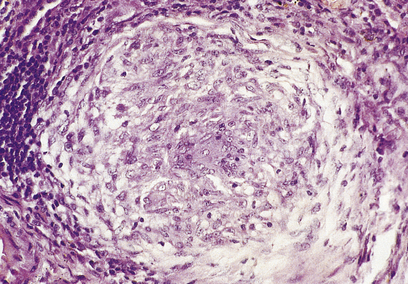

A granuloma is an aggregate of epithelioid histiocytes (Fig. 10.20). It may also contain other cell types such as lymphocytes and histiocytic giant cells. Granulomatous diseases comprise some of the most widespread and serious diseases in the world, such as tuberculosis and leprosy.

image

Fig. 10.20 A granuloma: a collection of epithelioid histiocytes. This example is from a case of sarcoidosis involving the liver.

Epithelioid histiocytes

Named for their vague histological resemblance to epithelial cells, epithelioid histiocytes have large vesicular nuclei, plentiful eosinophilic cytoplasm and are often rather elongated. They tend to be arranged in clusters. They have little phagocytic activity, but appear to be adapted to a secretory function. The full range, or purpose, of their secretory products is not known, although one product is angiotensin converting enzyme. Measurement of the activity of this enzyme in the blood can act as a marker for systemic granulomatous disease, such as sarcoidosis.